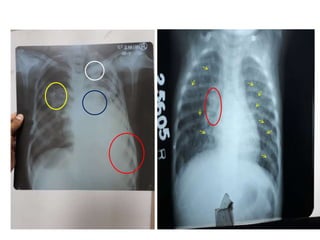

1.Infiltrate or consolidation - Opacification of airspaces within

the lung parenchyma

Chest x-ray of Ghon's complex of active tuberculosis

2. Any cavitary lesion

3. Nodule with poorly defined margins

4. Pleural effusion

5. Hilar or mediastinal lymphadenopathy (bihilar

lymphadenopathy) with or without associated atelectasis or

consolidation.

6. Linear, interstitial disease (in children only)

7. Other - Miliary TB. Miliary findings are nodules of millet size

(1 to 2 millimeters) distributed throughout the parenchyma

TUBERCULOSIS

1.Infiltrate or consolidation- Opacification of airspaces within the lung parenchyma Chest x-ray of Ghon's complex of active tuberculosis 2. Any cavitary lesion 3. Nodule with poorly defined margins 4. Pleural effusion 5. Hilar or mediastinal lymphadenopathy (bihilar lymphadenopathy) with or without associated atelectasis or consolidation. 6. Linear, interstitial disease (in children only) 7. Other - Miliary TB. Miliary findings are nodules of millet size (1 to 2 millimeters) distributed throughout the parenchyma TUBERCULOSIS